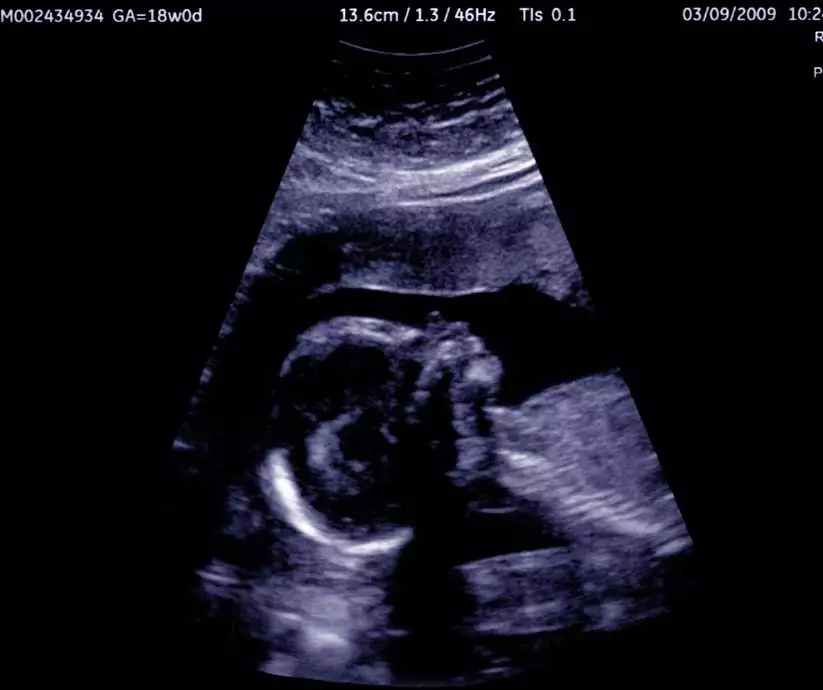

Zmiany u dziecka w 4 miesiącu ciąży

• Ciało zaczyna być większe niż głowa. Pod koniec tego miesiąca płód ma już 12,5–14 cm długości i waży około 150 g.

• Płód jest znacznie bardziej aktywny - porusza się częściej, energiczniej i z lepszą koordynacją. Nie pozostaje nieruchomy dłużej niż 3 lub 4 minuty. Czas przygotować się na rewolucję w brzuszku!:)

Zaczynasz odczuwać pierwsze ruchy płodu!

W miarę rozwoju tkanki mięśniowej płód coraz intensywniej się rusza. Okres między 14. a 17. tygodniem życia płodowego to czas największej ruchliwości Twojego dziecka. Korzysta on z tego, że w macicy ma jeszcze sporo miejsca i doskonali swój coraz bogatszy repertuar: przeciąga się, wygina grzbiet, porusza ramionami, wyciąga nogi, obraca się z boku na bok, obraca głowę, a nawet wykonuje salta.

Począwszy od 15. tygodnia życia płodowego macica dotyka ściany brzucha i matka może zacząć odczuwać ruchy dziecka, zwłaszcza jeśli jest w ciąży po raz kolejny (u pierworódek następuje to 2–3 tygodnie później). Z badań wynika, że ulubioną porą gimnastyki malców jest północ.